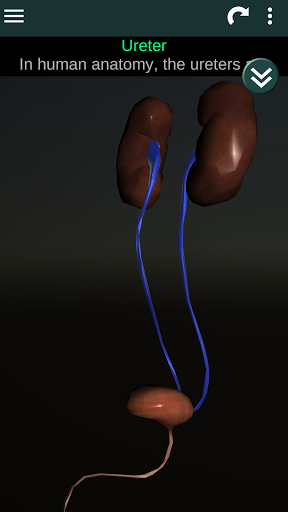

Menampilkan model anatomi 3D dari organ utama tubuh manusia dan penjelasannya masing-masing.

Apa yang ada di aplikasi?

* Sistem reproduksi, yang meliputi organ reproduksi pria dan wanita.